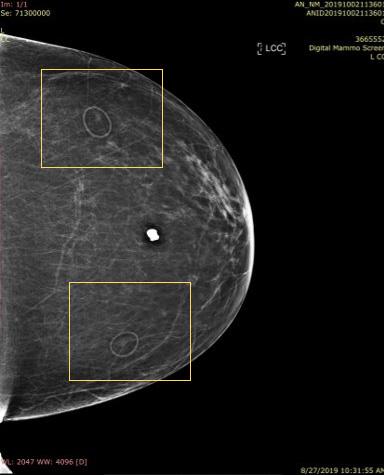

2-D mole marker used in 3-D, Slice 1 of 59

As radiologists reviewed the 3-D images, they began to realize that dense objects, such as calcifications, biopsy clips, surgical clips and the numerous skin markers that they had been using could generate artifacts that made interpreting the images harder.

Dense Object Artifact — the Slinky Effect

In particular, because they are larger than calcifications and clips, the skin markers3 that were used to indicate skin lesions, scars, sites of a palpable mass or pain caused significant artifacts called a ring down effect that caused distractions and limited visibility of underlying tissues.

“The biggest problem with the 2-D markers being used on the 3-D examinations is the ‘ring-down’ or ‘slinky effect’ that actually limits visualization of adjacent and underlying tissues, and is distracting, making one look at the artifact instead of the adjacent tissues,” she explained.